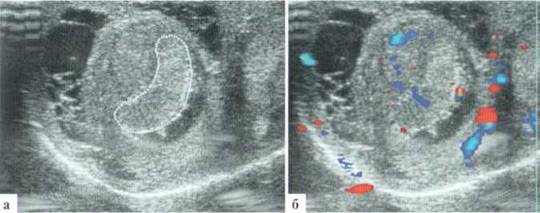

Орхит у детей встречается редко, чаще в подростковом возрасте, но зафиксирован и у новорожденных. Причина заболевания не всегда ясна, клинико-лабораторное подтверждение инфекции мочевыводящих путей, которой отводится известная роль в генезе орхитов и эпидидмитов, имеет место далеко не всегда. Характерны весьма разнообразные изменения структуры яичка в В-режиме: от редко выраженных до практически не дифференцируемых. В большинстве случаев имеет место некоторое увеличение яичка в размерах, преимущественно — в толщину, при этом оно приобретает шаровидную форму. Эхогенность паренхимы может оставаться нормальной, может диффузно понижаться. Всегда имеется значительное усиление сосудистого рисунка в паренхиме яичка. Часто определяется некоторое снижение RI артериального тестикулярного кровотока, но, строго говоря, количественная оценка тестикулярного кровотока при гиперемии яичка у детей с орхитами редко дает принципиально новую информацию для оценки состояния пораженного органа. Часто определяется утолщение оболочек яичка за счет их отека и небольшое количество жидкостного содержимого в оболочках (рис. 2.3.1).

Рис. 2.3.1. Орхит слева у ребенка 11 лет: а, б — правое неизмененное яичко 32x15 мм; в, г — левое яичка увеличено в размерах до 42x26 мм, паренхима гомогенная, без значительных структурных изменений, резко выраженное диффузное усиление сосудистого рисунка

Весьма демонстративным является поперечное сканирование мошонки, когда датчик располагается перпендикулярно ее шву, и в поле сканирования попадают одновременно оба яичка или хотя бы их внутренние фрагменты. Изменение формы яичка и интенсивности интратестикулярного сосудистого рисунка не вызывают сомнения (рис. 2.3.2).

Рис. 2.3.2. Поперечное сканирование по передней поверхности мошонки у ребенка 13 лет с правосторонним орхитом с одновременной визуализацией фрагмента правого (D) и левого (S) яичек